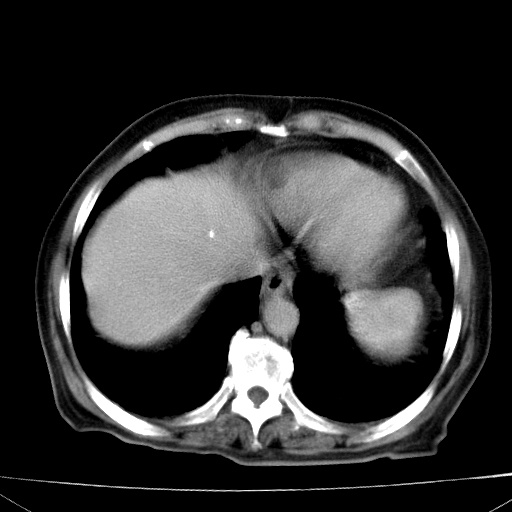

网站人气太旺!昨天的帖子就沉到海底,只好再发贴!ct18338:女 78岁,肝胆病变,已增强,再会诊!原帖链接:http://www.radida.com/bbs/forum.php?mod=viewthread&tid=50032

1)考虑胆囊癌侵犯肝脏并肝门区、腹膜后及右侧膈角后淋巴结转移。2)肝左叶近肝顶部囊肿。3)肝左叶肝内胆管结石。4)左肾近下极囊肿。